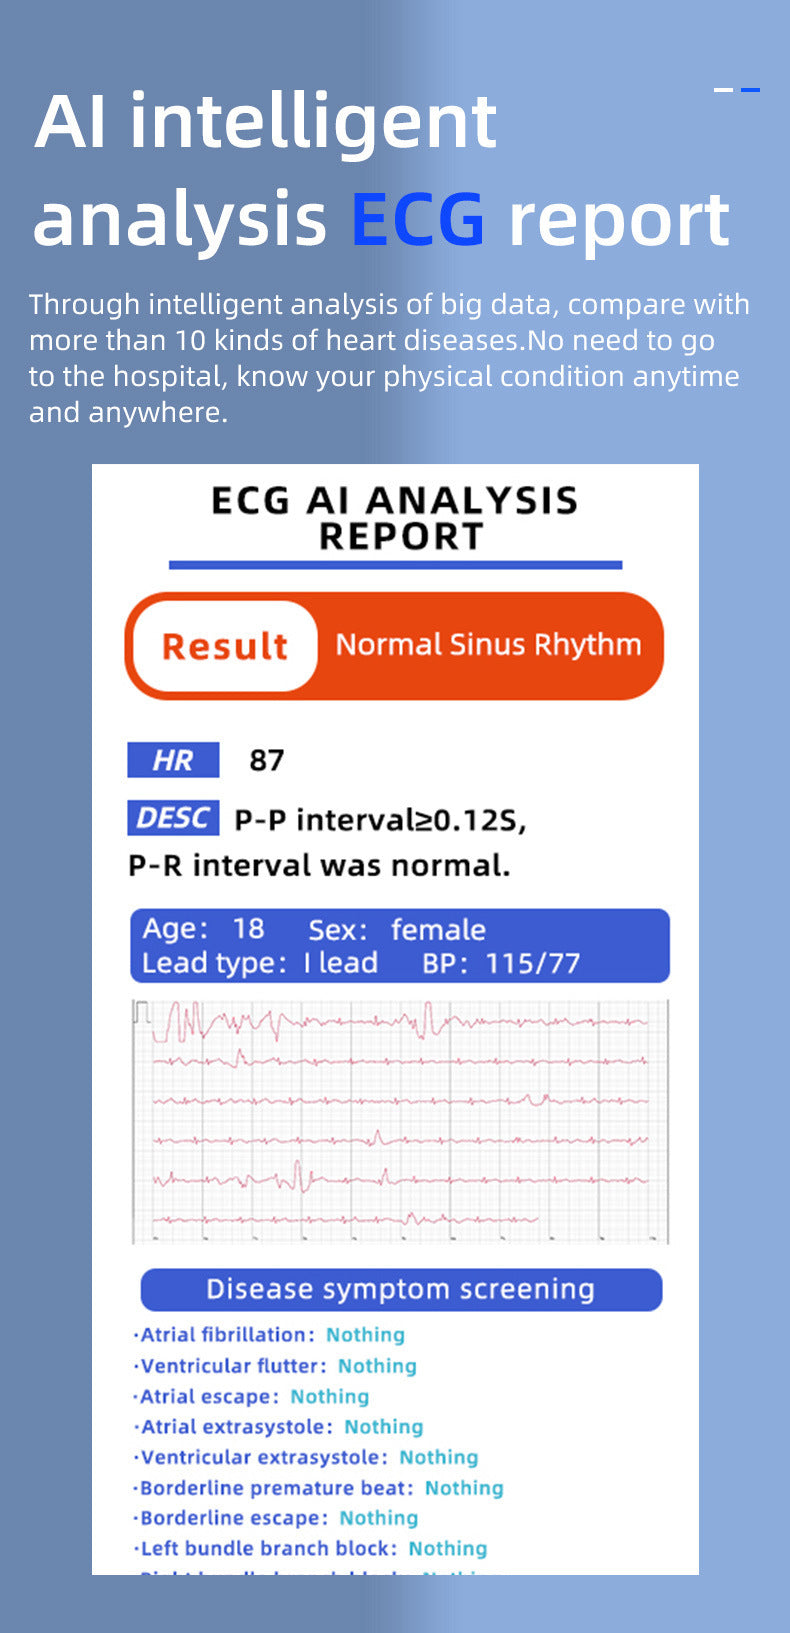

KS03 Smart Watch Heart Rate Blood Glucose Blood Oxygen ECG Monitoring

KS03 Smart Watch Heart Rate Blood Glucose Blood Oxygen ECG Monitoring

€74,95KS03 Smart Watch Heart Rate Blood Glucose Blood Oxygen ECG Monitoring

€74,95 -